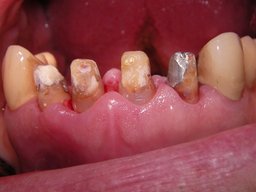

Weil auch die anderen Schneidezahnkronen (12-22) durch Randreparaturen und den schlechten Randschluß erneuerungsbedürftig aussahen, wurden 4 Einzelkronen geplant. Vorher hieß es aber noch, die schlechte Wurzelfüllung im Zahn 12 (Röntgenbild links) besser zu machen. Hierfür wurden am 17.2.06 die alten Kronen 11 und 12 entfernt. Rechts das Bild nach Entfernung von alten Füllungen und Karies.